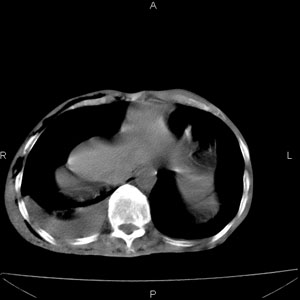

患者男,77岁,于3日前从树上摔下,头部查ct示蛛血,硬膜下出血,上腹部ct未见明显异常,右侧胸腔积液,左侧如常。肺部拍片示右侧肋骨多发骨折住院后今日来查肺部ct,我看到的是1。右侧胸腔血气胸并右肺上叶,中叶压缩性肺不张,2。右肺下叶肺挫伤并多发肋骨骨折,肌内及皮下积气3。左侧少量胸腔积液,我想请教的是3天前左侧胸腔里没有积液今天怎么出现了呢,是什么原因呢?请讨论。

1、外伤出血需要一定的时间

2、气胸存在时间长了,产生的胸膜渗液

支持楼主意见。外伤可有迟发性的改变。

考虑外伤性迟发性胸腔积液。